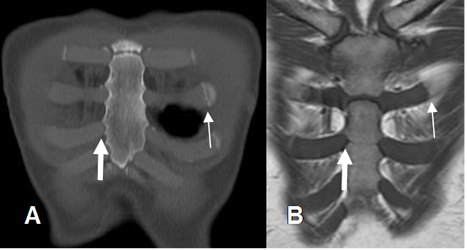

Fig 10. Articulación costoesternal normal.

A: TAC reconstrucción coronal y B: RM coronal en T1. Articulaciones costocondrales (Flechas delgadas) y condroesternales normales. (Flechas gruesas).